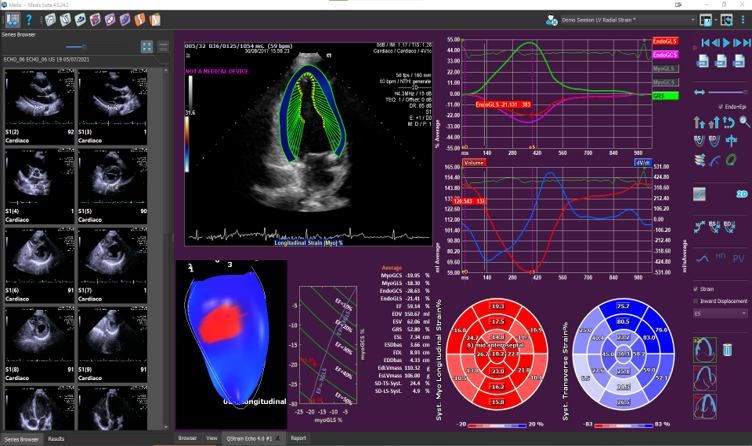

Medis Suite Ultrasound is the latest addition to the Medis Suite portfolio for cardiovascular imaging. Based on 20 years of developments and innovations, we bring you the latest image post-processing tools in advanced cardiac deformation analysis for echo. Medis Suite Cardiac Ultrasound (Echocardiography) is currently available for research use. Medis Suite Ultrasound is a continuation of over 20 years of innovative algorithms and ground-breaking work in Echocardiography software by AMID. AMID was acquired by Medis in 2020.

- Considered by many the gold standard vendor independent software for advanced cardiac deformation analysis, providing deeper insight into heart function

- Echo Strain is available together with MR Strain and CT Strain, a truly multimodality approach for advanced cardiac deformation imaging, using the same technology optimized for the different modalities

- Allows the quantitative evaluation of the Left Ventricle, Right Ventricle and the Left Atrium OEM solution. See the applications below for further details